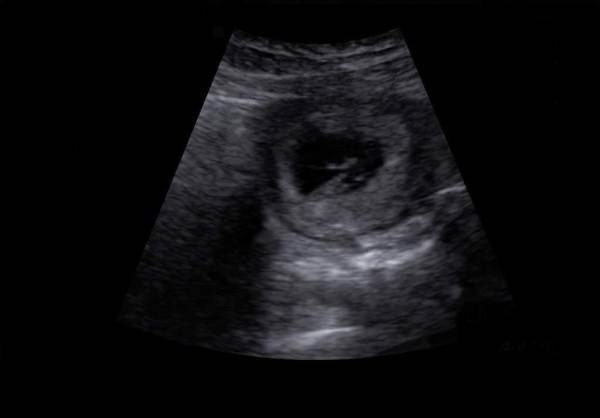

My Early Miscarriage

I hesitated to write this post, but I know that if a momma out there was suffering a miscarriage and could find comfort or camaraderie in my story, then I would want to help her. I would want her to know that she isn't alone in her pain and in her grief. And I would... Continue Reading →